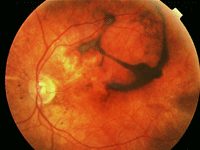

En la fase de convalescencia (Figura 4) aparece despigmentación de la piel y la úvea.

Figura 4. Cambios pigmentarios del fondo de ojo en la enfermedad en fase de convalescencia.